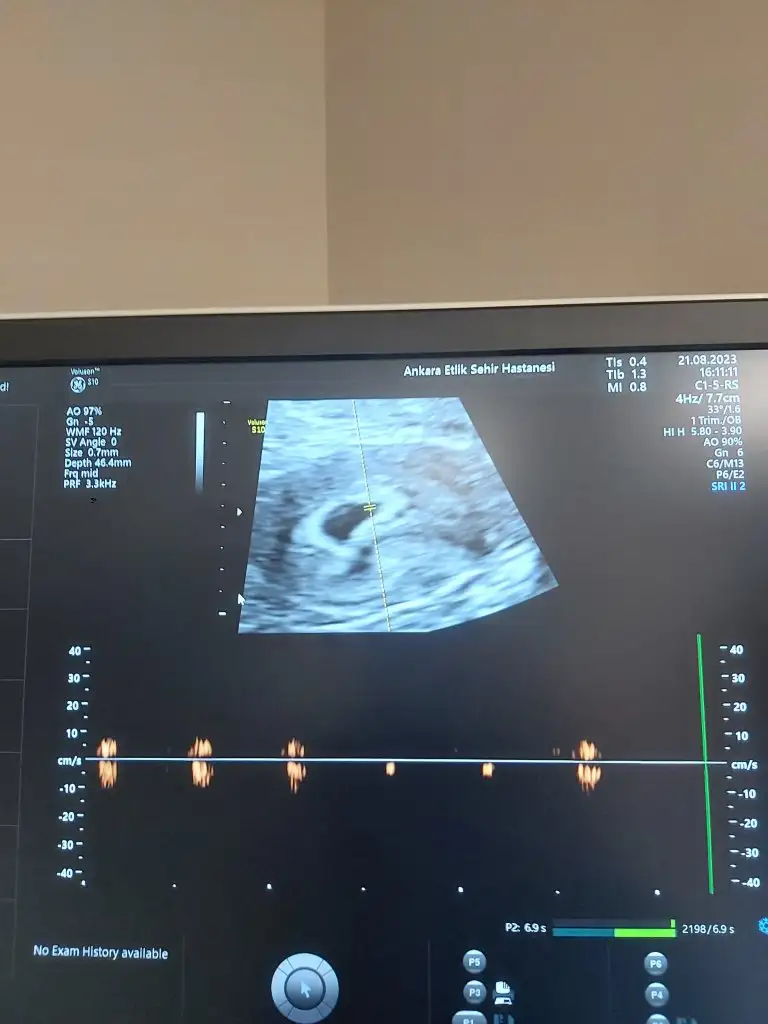

Bende böyle bisey duymuştum benim de 140 ti henüz cinsiyeti belli değil 8 haftalik daha Allah hayirlisini versin size deArkadaşlar bişey okudum bugün bebek kalp ritmi 140 ise kız, 140'ın altında ise erkekmiş. Sizin kalp atışları kaç ölçüldü?

Bu bebeğin kalp atış sayısı bebeğin haftasına göre değişen bir şey . Hangi haftayı baz alacağız 140 içinBende böyle bisey duymuştum benim de 140 ti henüz cinsiyeti belli değil 8 haftalik daha Allah hayirlisini versin size de

peki benim doktorun kalp atışını dinletmeyip sadece kalp atışını göstermesiBu bebeğin kalp atış sayısı bebeğin haftasına göre değişen bir şey . Hangi haftayı baz alacağız 140 için

Ben gittiğimde 6 haftalikti 140 atıyordu doktora sordum kız mı erkek mi diye 2 hafta sonraki kalp atışı na göre belli olur dedi ama bilmiyorim yinede de pazartesi günü kontrol e gidicemBu bebeğin kalp atış sayısı bebeğin haftasına göre değişen bir şey . Hangi haftayı baz alacağız 140 için